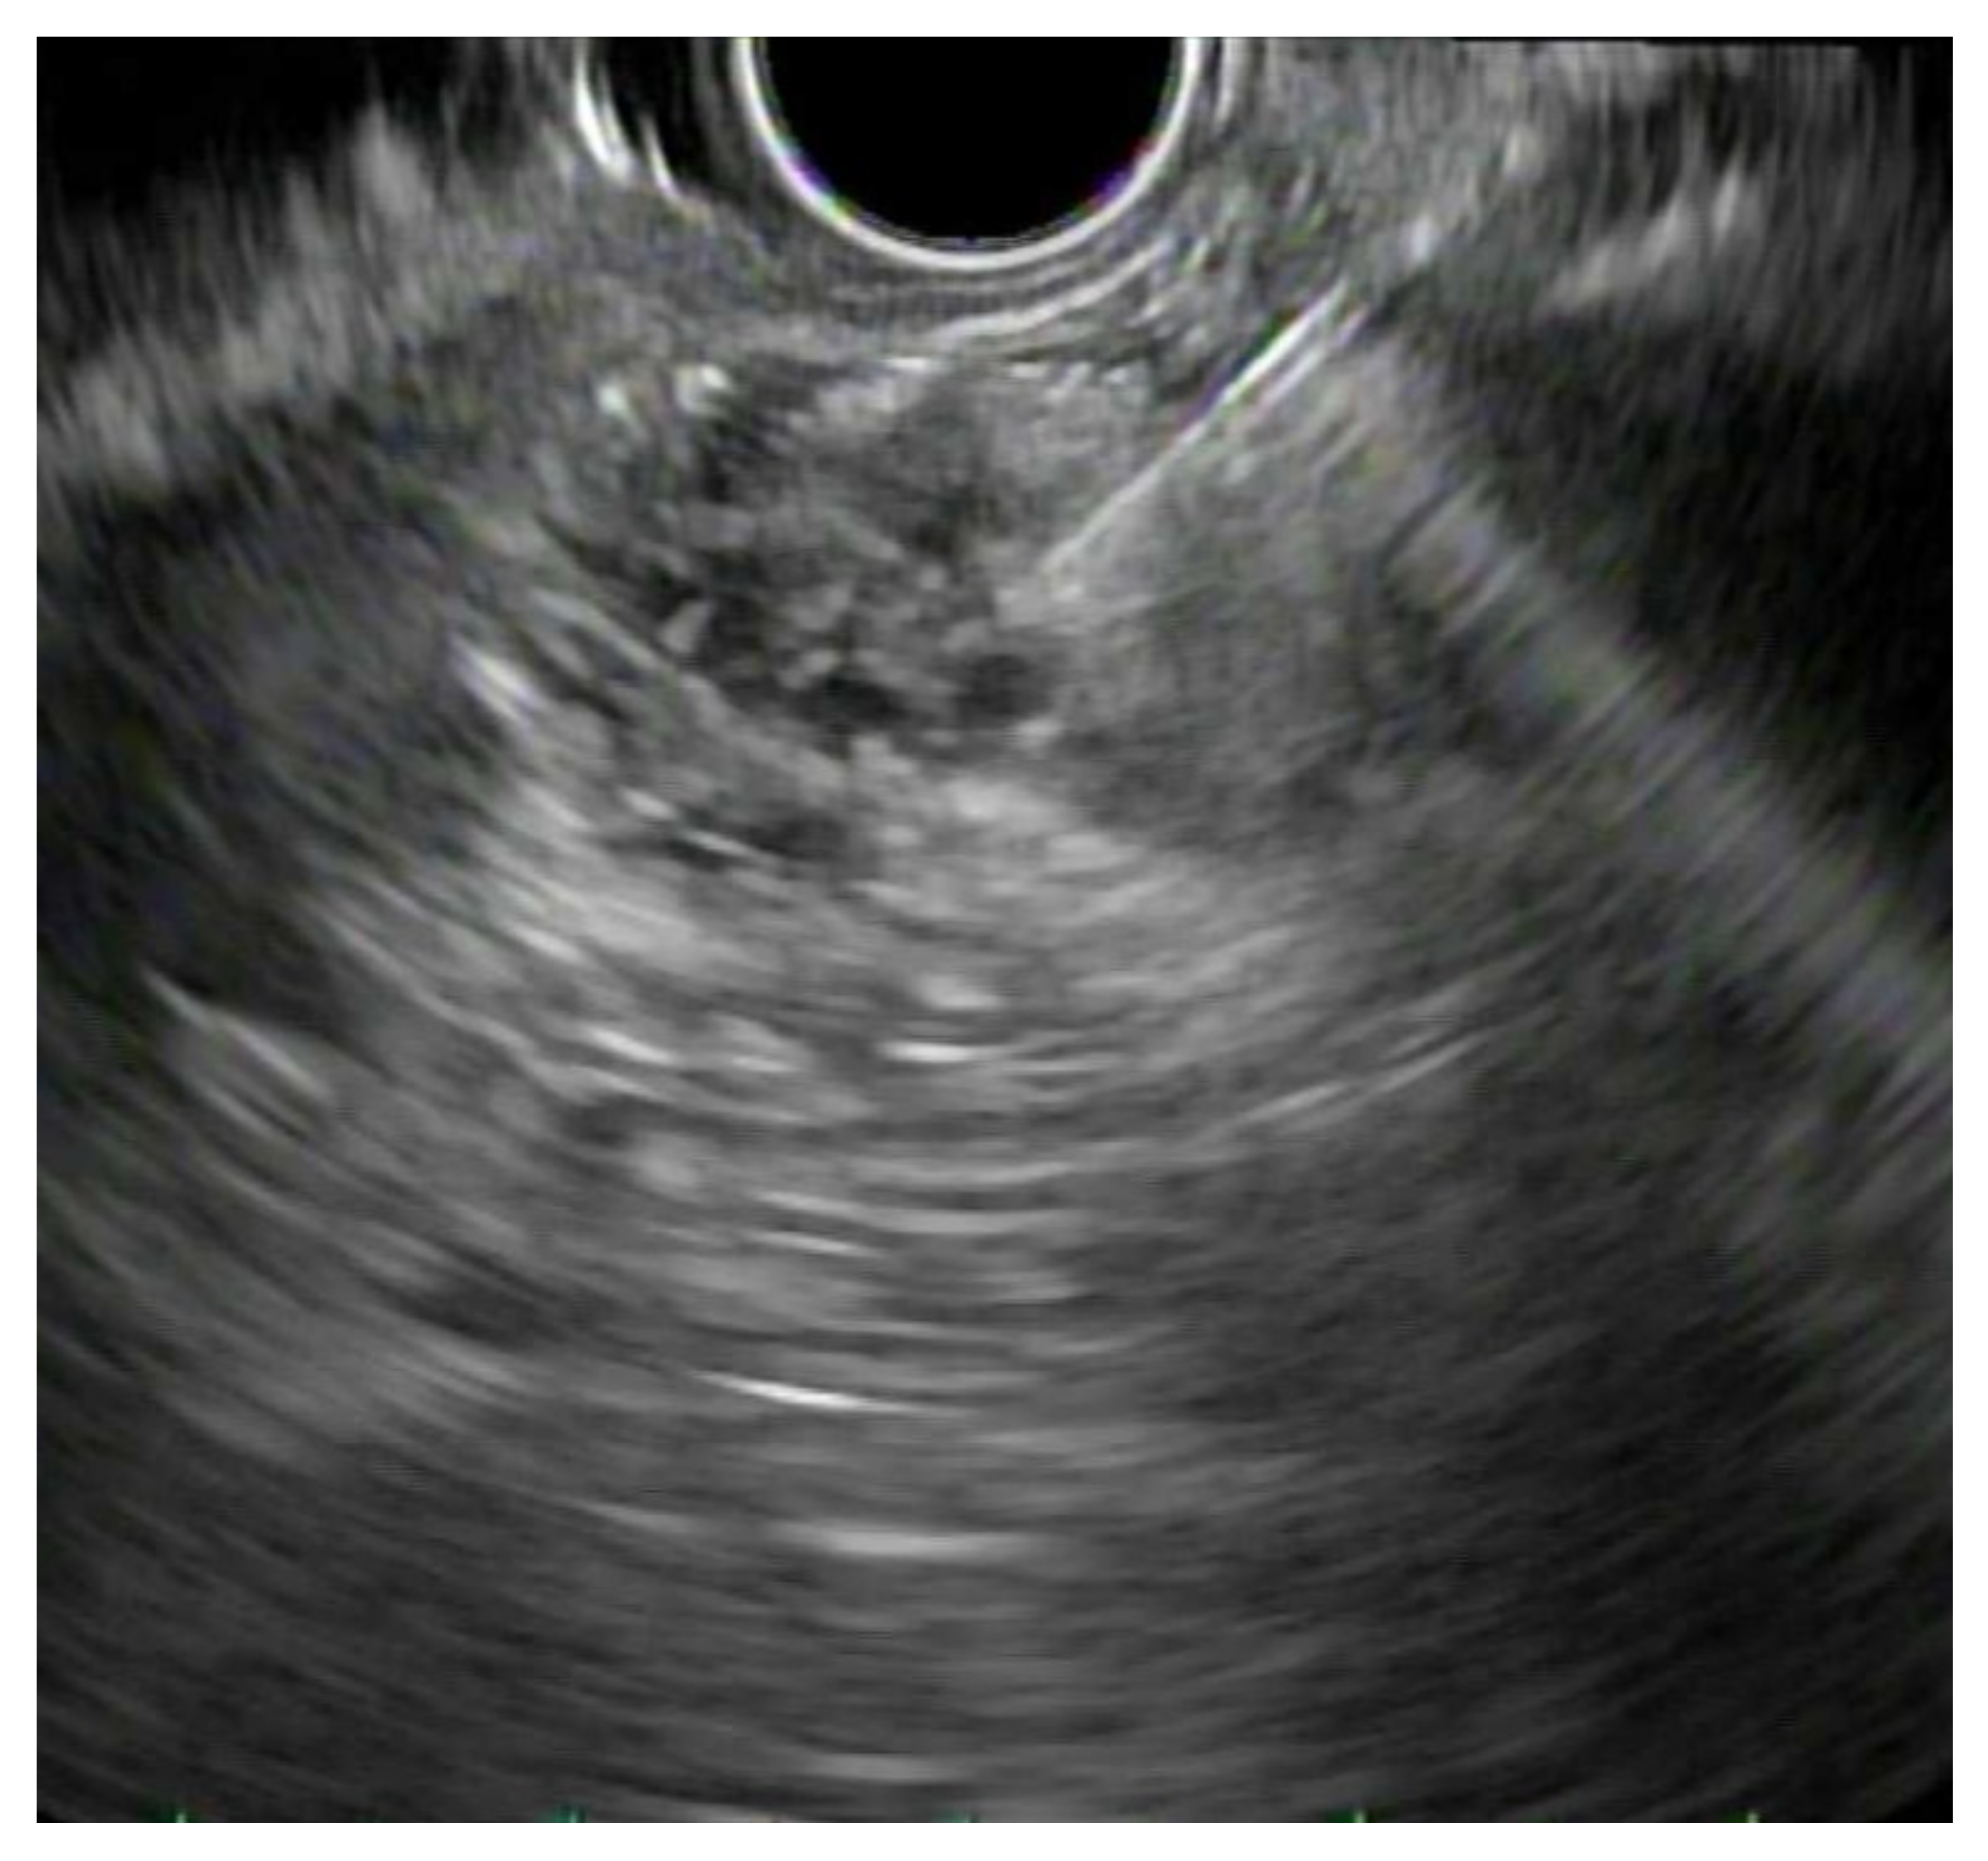

4.2. Biliary Obstruction: ERCP vs. EUS-BD